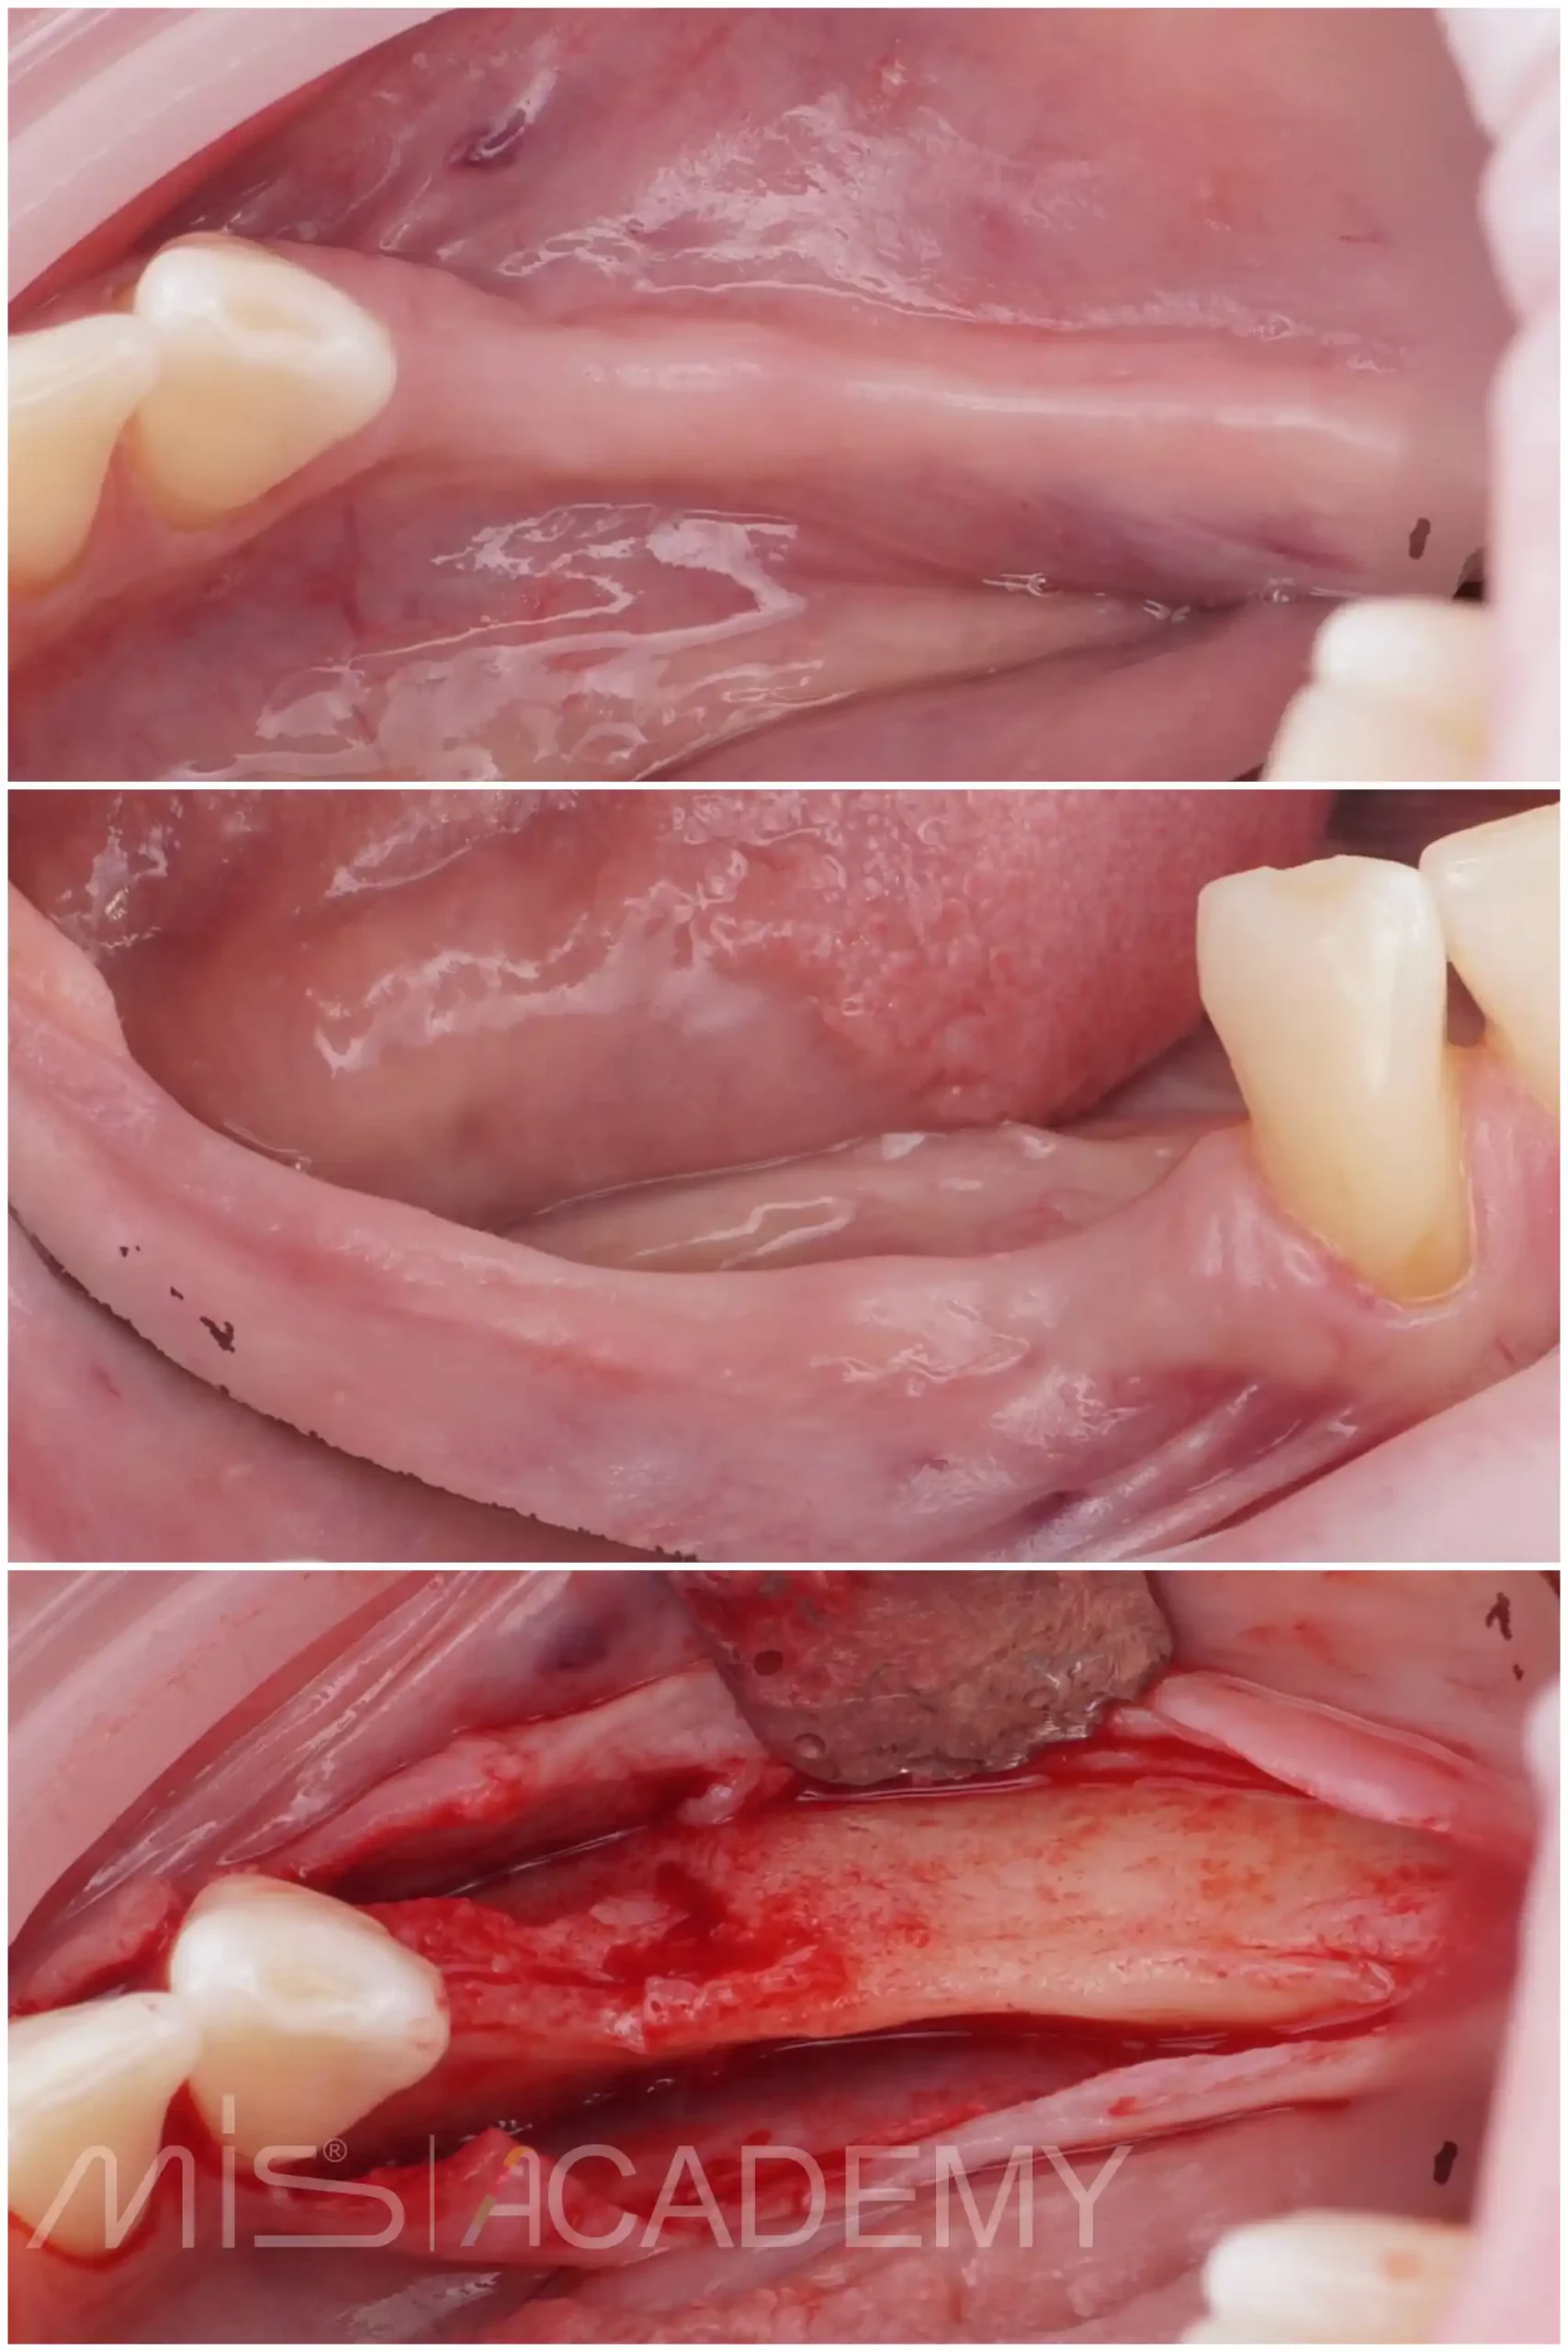

Восстановление дефекта на нижней челюсти:

— Gen-os.

— Ауто и ксено Lamina curved, которая была зафиксирована надкостничными швами.